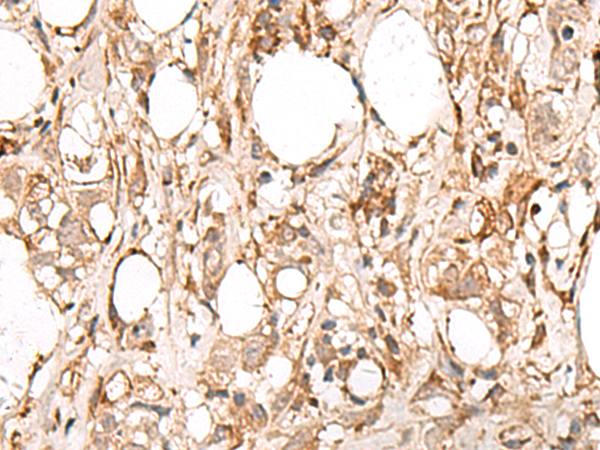

IHC (Immunohistochemistry)

(The image is immunohistochemistry of paraffin-embedded Human esophagus cancer tissue using (FBXW8 Antibody) at dilution 1/65.)